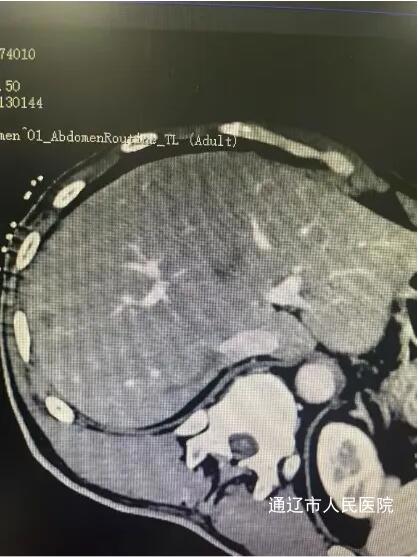

近日,我院肝胆胰外科成功实施了全市首例CT引导下肝肿瘤纳米刀消融术,标志着我院肝胆胰外科在肿瘤微创消融领域迈上新台阶,填补了本地区医疗技术空白。该患者男性,因腹胀于我院就诊,完善相关检查诊断结肠癌伴肠梗阻,肝占位性病变考虑转移瘤,讨论病情后决定一期行腹腔镜下根治性右半结肠切除术,术后复查腹部增强CT、增强肝脏MRI提示肝脏转移瘤有进展趋势,遂行CT引导下肝肿瘤纳米刀消融术。

手术过程中,患者行全身麻醉,在解放军总医院肖越勇教授指导下,我院肝胆胰外科主任医师郭雅明、手术麻醉科副主任医师高飞、CT室医护团队在CT引导下确认病灶位置并进针,确保电极区域完全包裹肿瘤后开始消融。消融过程中电流上升反馈良好,术后即刻增强CT显示消融范围覆盖病灶,周围血管、胆道结构完好无损伤,出现明显气体影,消融效果良好。消融完成后,退出穿刺针,手术顺利结束,术中麻醉效果满意,生命体征平稳,麻醉恢复后无腹痛腹胀,恶心呕吐等不适。术后给予对症支持治疗,患者恢复良好。和传统的消融治疗方式不同,纳米刀消融技术是通过脉冲电场导致细胞不可逆电穿孔,从而实现肿瘤组织杀伤,是一种非热选择性物理消融技术,可在实现消融肿瘤的同时,保留肿瘤周围的重要管道结构(血管、胆管和神经)完整性,并且无热沉效应,消融肿瘤细胞,适用于消融治疗靠近肝门、胆囊、膈肌和结肠等肝脏特殊部位的肿瘤有着独特的优势。纳米刀消融手术为现阶段先进、安全的肿瘤消融技术,它为无法使用传统手术方式的特殊部位癌症患者提供了新的治疗方式,还具有能够选择性消融,时间短、创口小等优点,一定程度上能够改善生活质量,延长生存时间,纳米刀消融对不能手术的肝癌、肺癌特别是胰腺癌具备较大的技术优势。此次全市首例纳米刀消融术的开展,标志我院微创介入技术取得重大突破,也为疑难肿瘤患者提供了更为先进技术的诊疗手段。